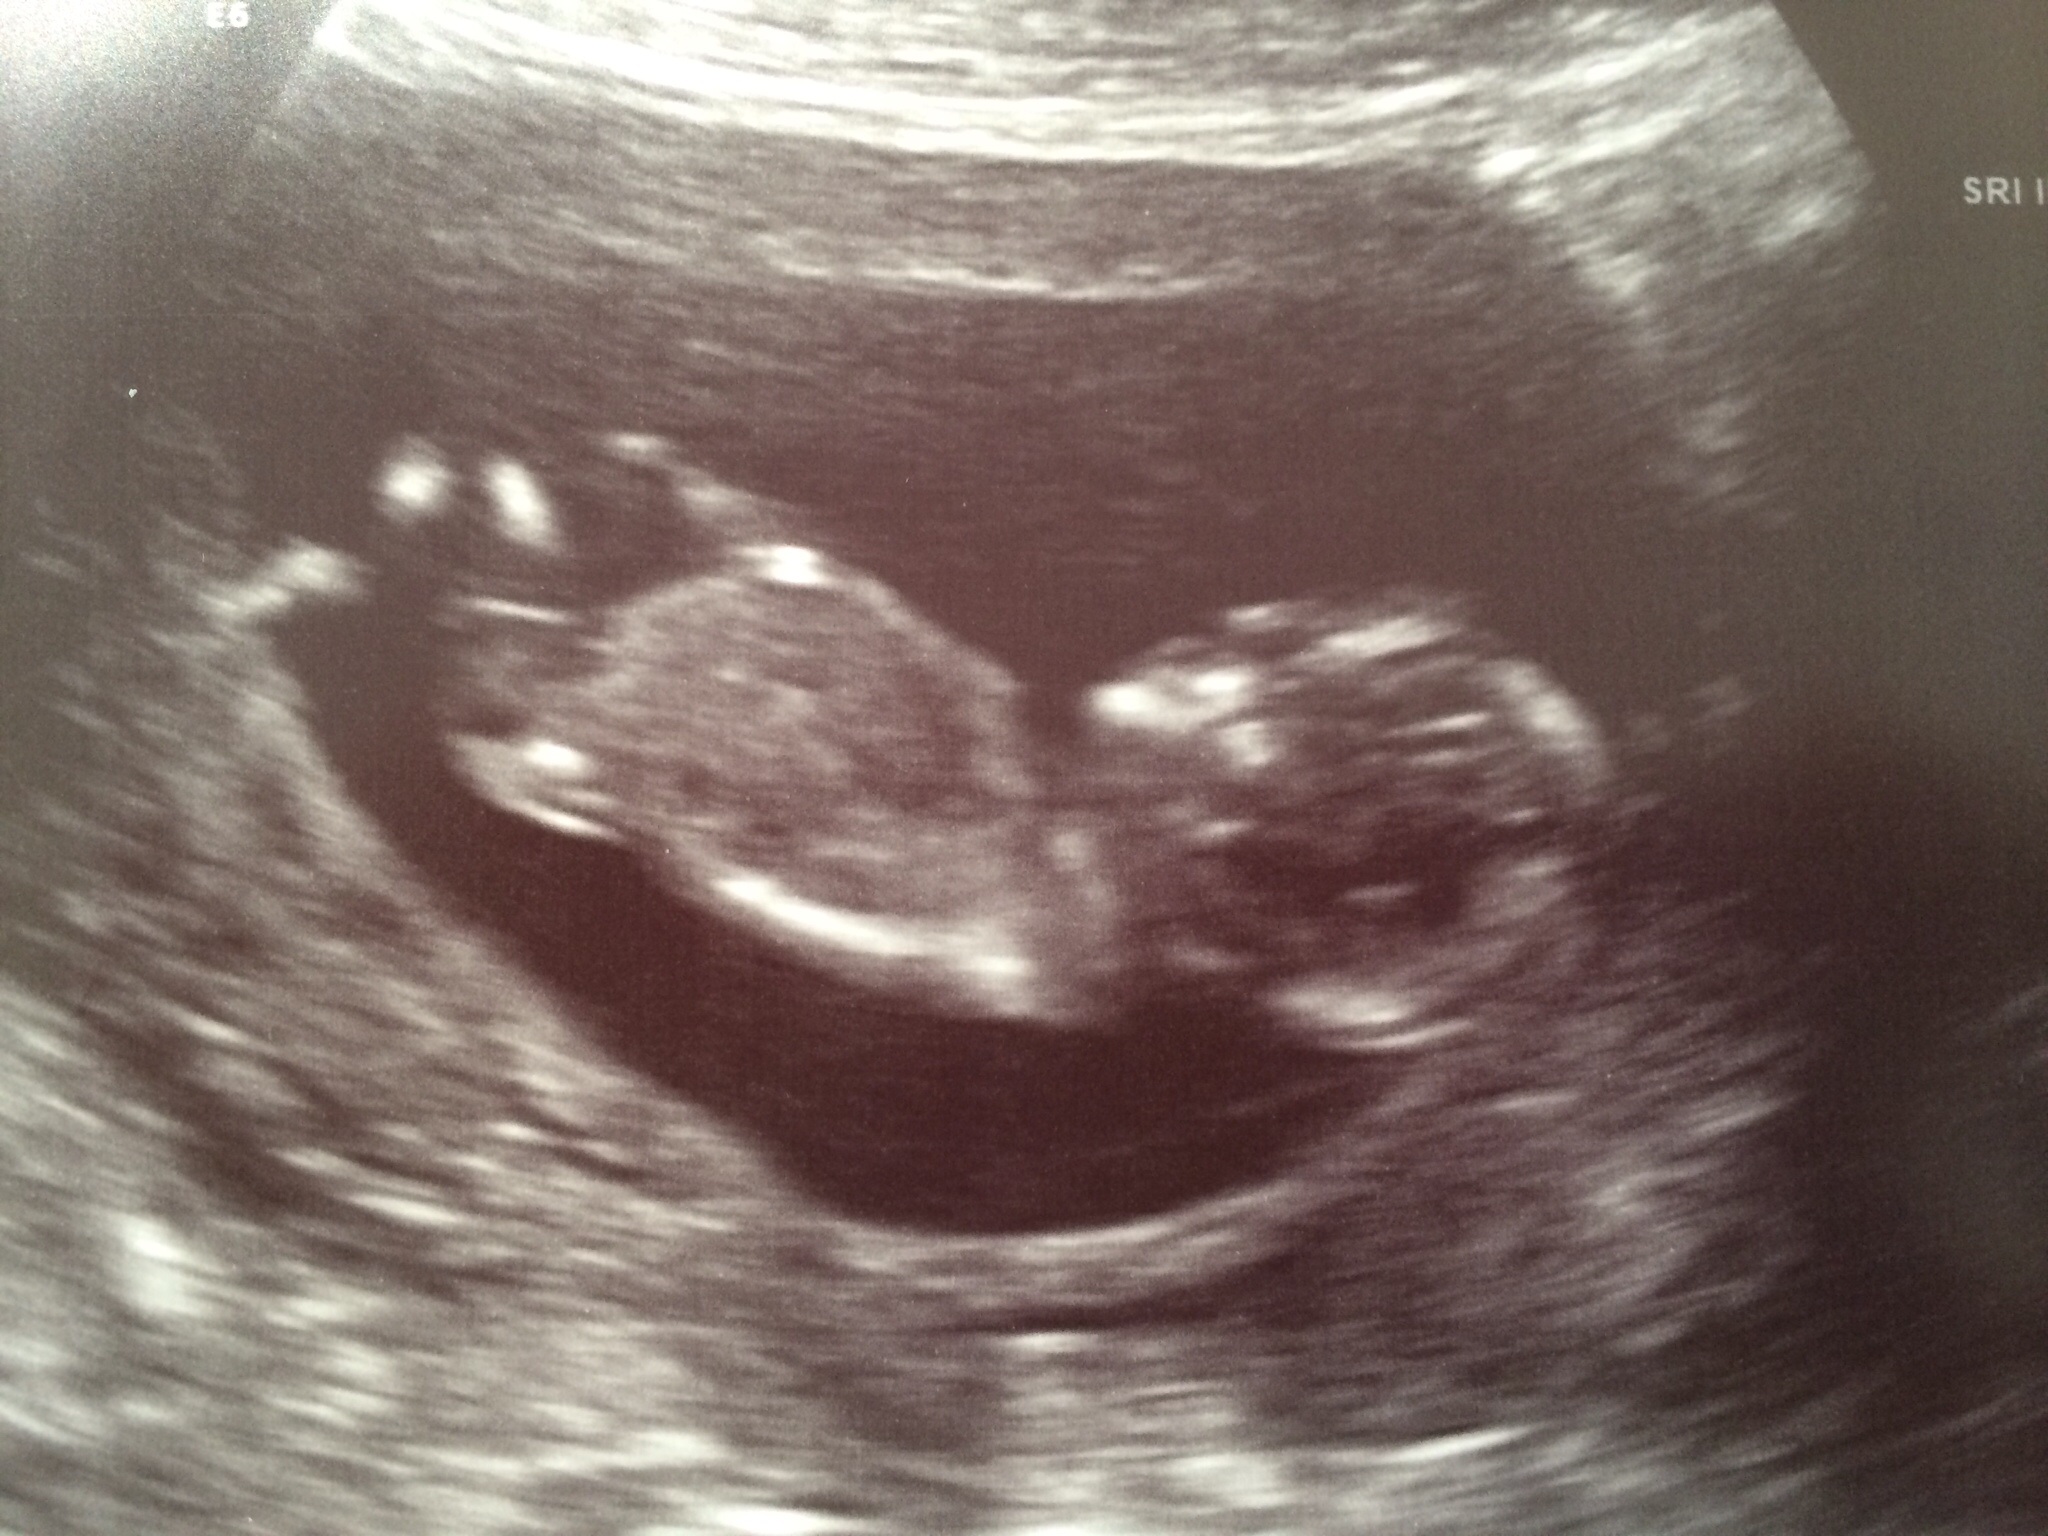

@pdtoast, great photos!! Are you team green? just wondering b/c according to the nub theory, it is very much obvious the sex of your LO.

Nope, we'll find out. I'm not familiar with that theory, but the US tech said that her guess would be boy although she emphasized that it's too early to make a definitive statement about sex. Not sure if that's what you were thinking too.

Yeah... I would be shocked if it's not a boy.